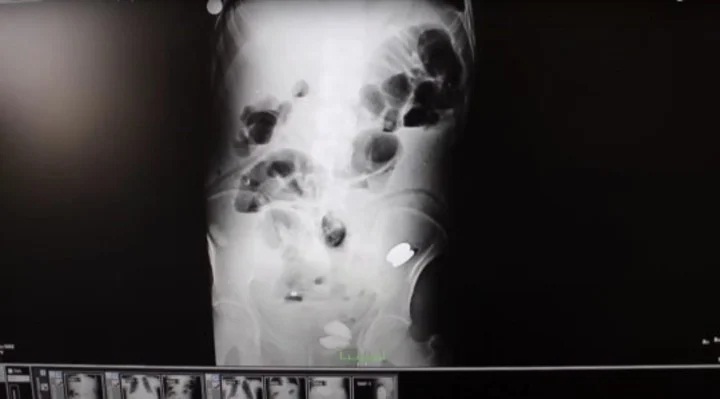

La sorpresa llegó cuando le realizaron al hombre un ultrasonido endoscópico (EUS) -combina la endoscopia y el ultrasonido- y una serie de radiografías. Los médicos quedaron desconcertados al descubrir 233 elementos en el estómago.

Monedas, clavos, pilas, fragmentos de vidrio, imanes, piedras y tornillos fue lo que los médicos hallaron dentro del estómago del hombre, al que identificaron solo como Z.

“Vimos que había dos piezas de metal y dos piedras de diferentes tamaños en el intestino grueso", agregó, y continuó: "También encontramos que había pilas, imanes, clavos, monedas, pedazos de vidrio y tornillos. Le limpiamos el estómago por completo".